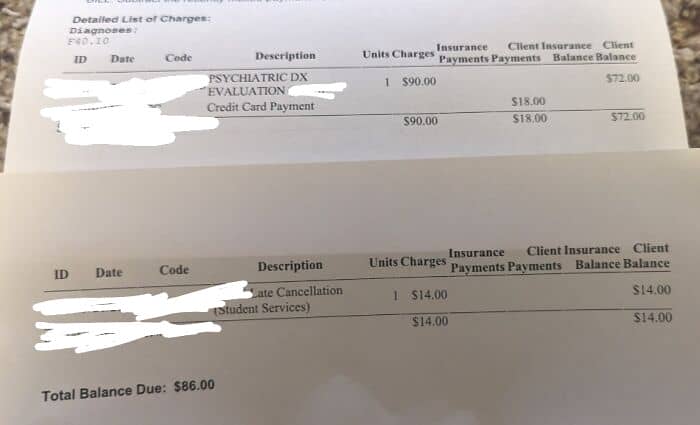

#94 Had 1 Appointment At A Psychology Center On Campus, Was Told It Would Only Be $18 And Paid That At The Appt. Got Sick, Had To Cancel My Next One. Now I Have An $86 Bill I Cant Afford

I went to a psychology center at my university for an intake appointment due to pretty severe anxiety. They told me it was sliding scale payments and due to my income would only be $18, so I went and that’s what they paid. I felt pressured by the therapist to schedule a second appointment so I did, even tho I did not like her very much. Day of I’m throwing up so I call and cancel, they just say okay. Now a few weeks later I have an $86 bill, $72 because apparently my appointment is somehow $90 instead of the $18 I was told and $14 for a cancellation fee. I’ll pay that fee, whatever, but I would never have scheduled an appointment if I knew it’d be $90 because I do not have that much money. I’m literally working two jobs and only eating twice a day to survive rn. I’m so pissed off at them sending me a bill way over what I was told weeks later and I genuinely don’t know how I’m going to pay it. It makes me sick just thinking about literally throwing away $86 for something I got nothing out of.